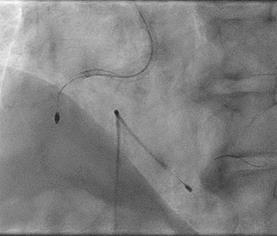

Can thiệp ngã ba động mạch liên thất trước và nhánh chéo 1 với hai stent có bọc thuốc bằng kĩ thuật cullote. Tiếp tục can thiệp động mạch vành phải với ống thông can thiệp (guiding catheter) (Cordis JR4 cm 6Fr) và dây dẫn (Asahi Sion 0.014”). Nong tổn thương bằng bóng 3.5 x 15mm (Neich Sapphire), bóng 4.0 x 12 (NC Quantum Apex), bóng cắt 3.5 x 15 (Cutting balloon, Angiosculpt) không làm vỡ được mảng vữa xơ. Quyết định dùng hệ thống khoan cắt mảng vữa xơ với dây dẫn mềm (Boston Scientific Rotablator Rotalink Plus) và mũi khoan (burr) 1.5mm. Tuy nhiên vì kích thước động mạch quá lớn nên mũi khoan đi qua tổn thương mà không chạm vào mảng vữa xơ được. Chuyển sang mũi khoan có đường kính lớn hơn 2.15mm với tốc độ khoan 150000 vòng /phút. Khi mũi khoa đi qua được 1/3 tổn thương thì không thể di chuyển được tiếp. Nhận định tại thời điểm đó là mũi khoan bị kẹt trong tổn thương tại đoạn giữa của động mạch vành phải. Ngay lập tức các bác sỹ có kinh nghiệm can thiệp trong bệnh viện được mời đến phòng can thiệp đồng thời thông báo cho các phẫu thuật viên tim mạch chuẩn bị trong trường hợp cần thiết. Bệnh nhân có biểu hiện đau tức ngực trái, tuy nhiên mạch và huyết áp tương đối ổn định, điện tim không thay đổi. Dòng chảy trong động mạch vành còn duy trì nhưng chậm TIMI 2. Sau khi hội ý, hướng xử trí đầu tiên là dùng dây dẫn cứng Conquest Pro (Asahi) để đi qua tổn thương nhưng không thành công. Sau đó chúng tôi quyết định cắt đoạn đầu của hệ thống nối mũi khoan, đưa ống thông heartrail (Terumo) sát vào mũi khoan nhằm thay đổi tư thế và cố định mũi khoan vào dây dẫn để đưa ra ngoài. Cuối cùng mũi khoan được đưa ra ngoài thành công. Tổn thương tiếp tục được nong bằng bóng cắt và bóng áp lực cao và đặt được giá đỡ kim loại (stent) bọc thuốc 4.0 x 26mm. Kết quả là động mạch vành được mở rộng hoàn toàn, bệnh nhân không còn đau ngực, huyết động ổn định.

Hình 1: A- hình ảnh động mạch vành trước can thiệp; B – dùng bóng cắt (cutting balloon) không phá vỡ được cấu trúc mảng vữa xơ; C – mũi khoan 1.5 không chạm vào được mảng vữa xơ vôi hóa; D – mũi khoan 2.15 bị tắc tại vị trí hẹp.